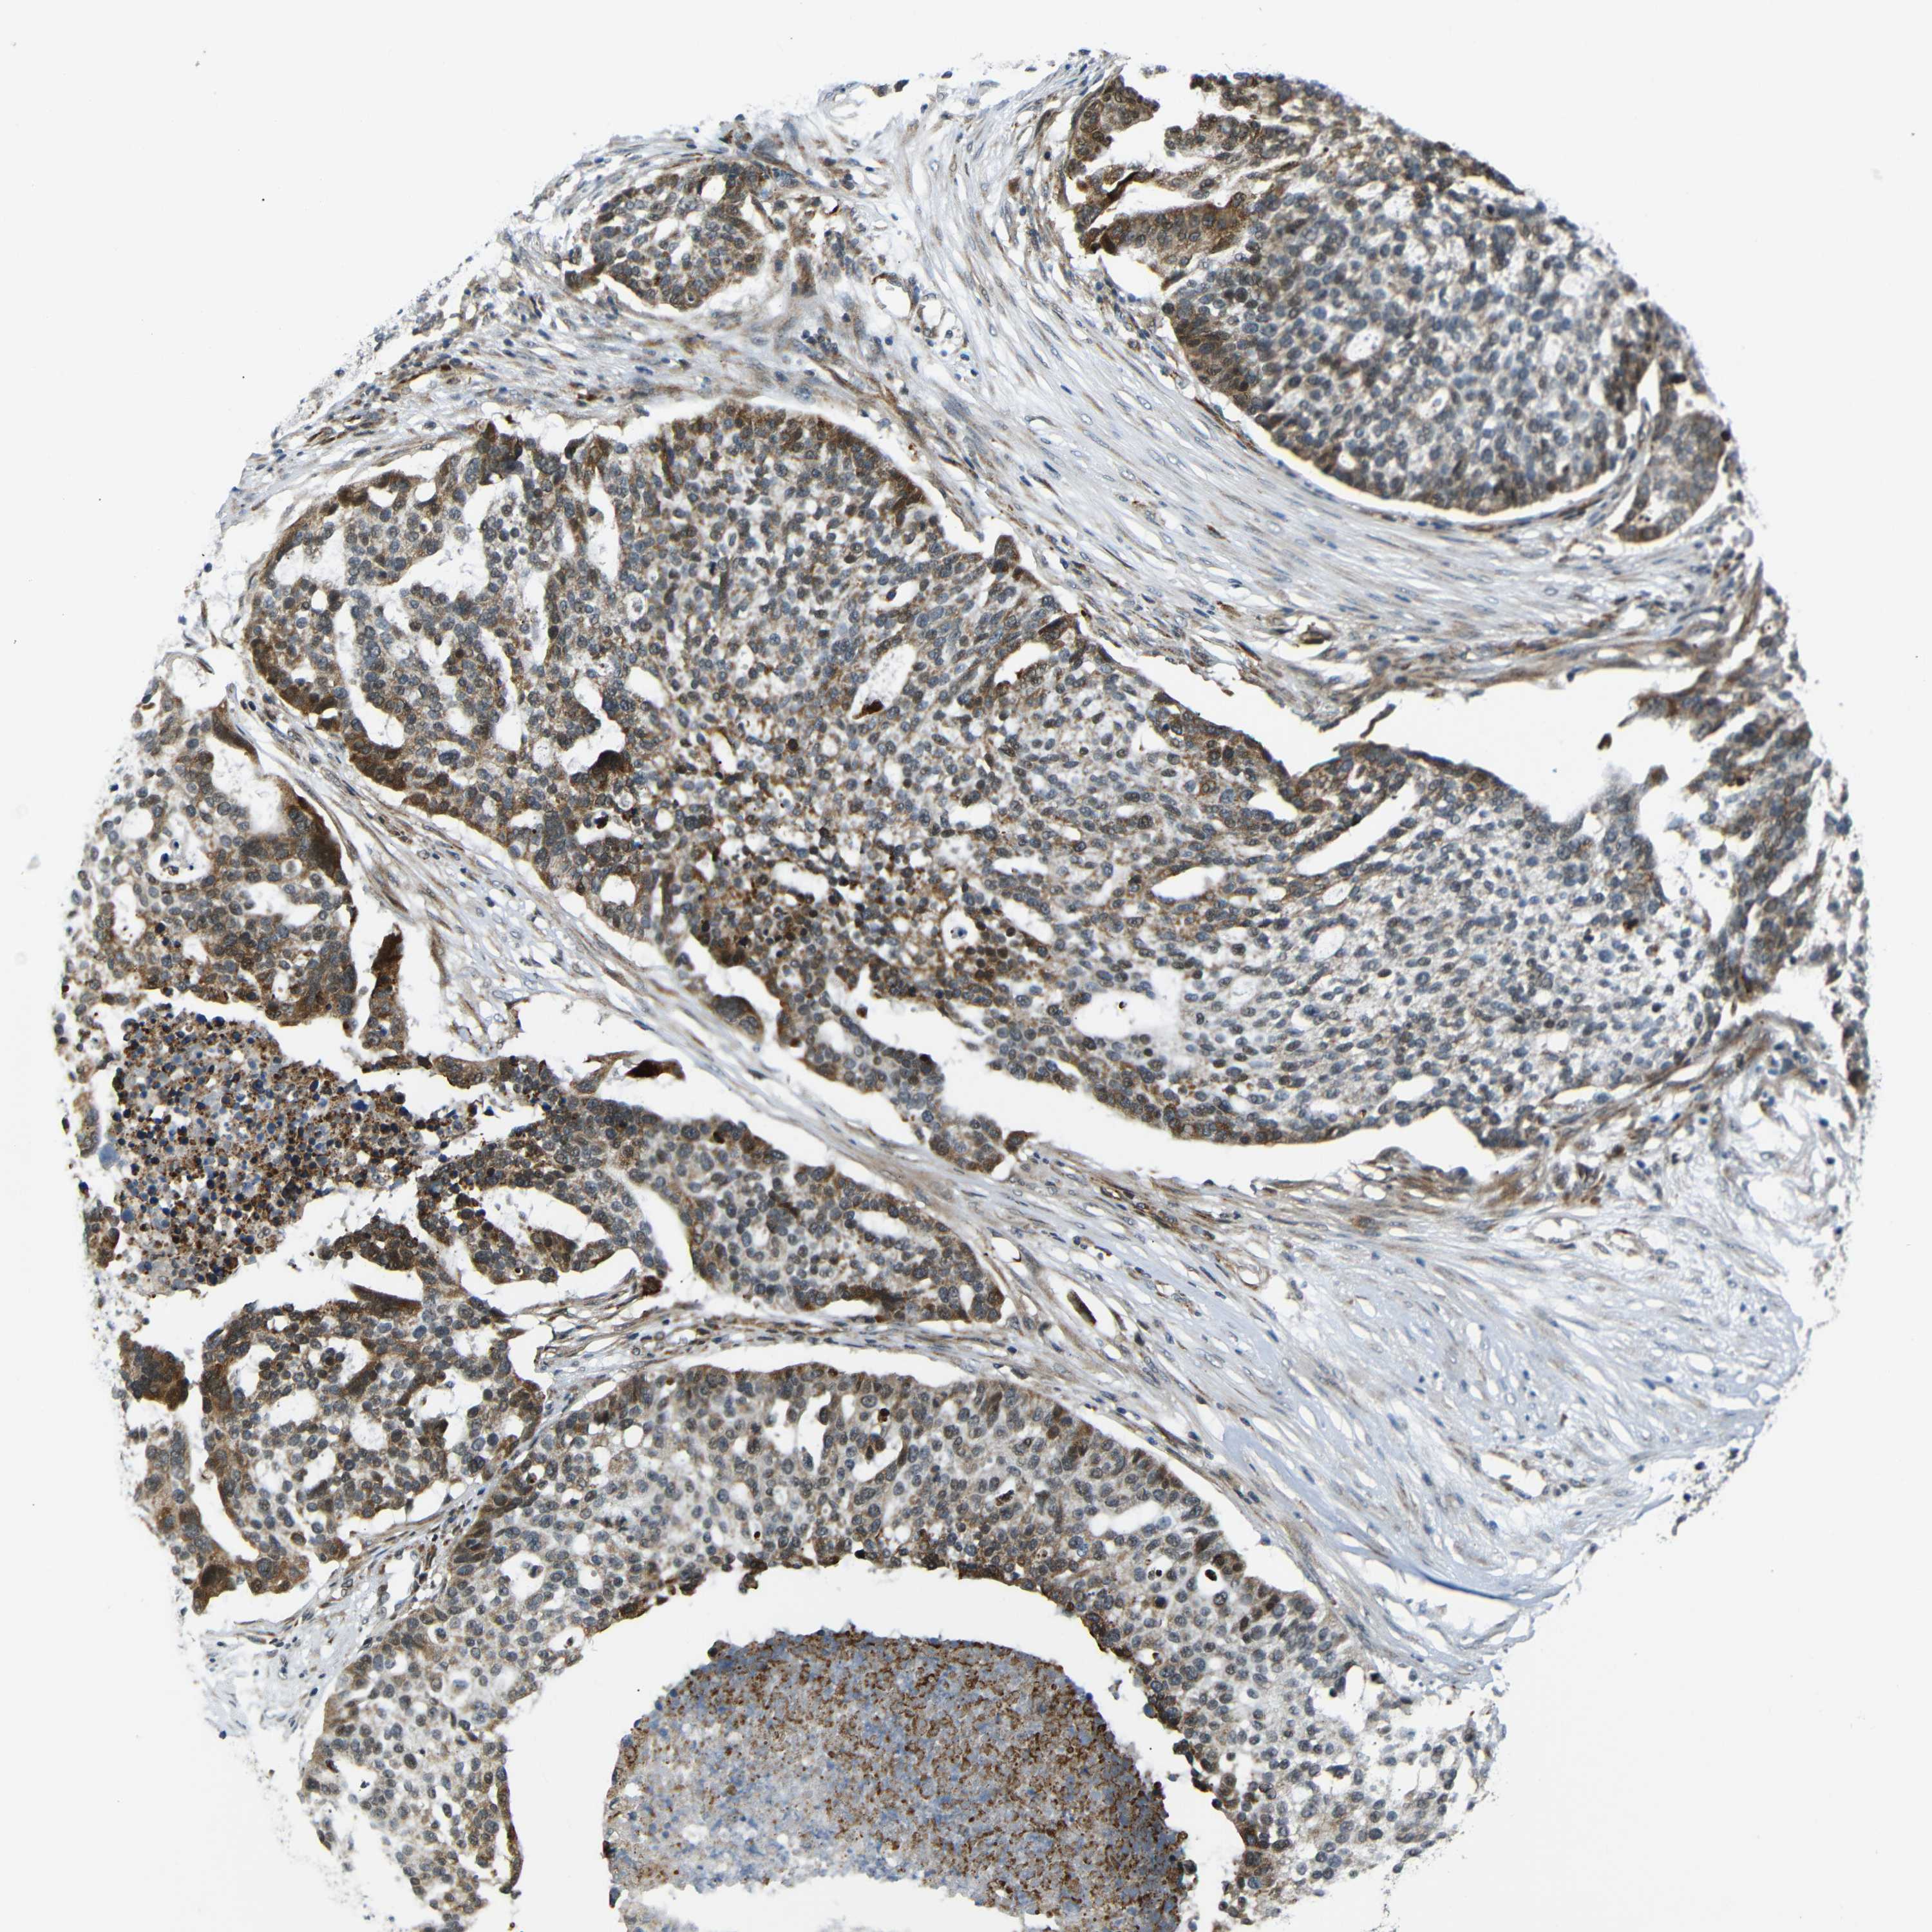

OVARIAN CANCER - Protein expressioni

A mouse-over function shows sample information and annotation data. Click on an image to view it in a full screen mode. Samples can be filtered based on level of antibody staining by selecting one or several of the following categories: high, medium, low and not detected. The assay and annotation is described here.

Note that samples used for immunohistochemistry by the Human Protein Atlas do not correspond to samples in the TCGA dataset.

Antibody stainingi

Antibody staining in the annotated cell types in the current human tissue is reported as not detected, low, medium, or high, based on conventional immunohistochemistry profiling in selected tissues. This score is based on the combination of the staining intensity and fraction of stained cells.

Each image is clickable and will lead to virtual microscopy that enables deeper exploration of all samples and also displays staining intensity scores, fraction scores and subcellular localization as well as patient and tissue information for each sample.

Antibody HPA013328

Staining

High

Medium

Low

Not detected

Intensity

Strong

Moderate

Weak

Negative

Quantity

>75%

75%-25%

<25%

None

Location

Nuclear

Cytoplasmic/membranous

Cytoplasmic/membranous,nuclear

Cystadenocarcinoma, serous, NOS

Carcinoma, endometroid

Cystadenocarcinoma, mucinous, NOS

Carcinoma, NOS